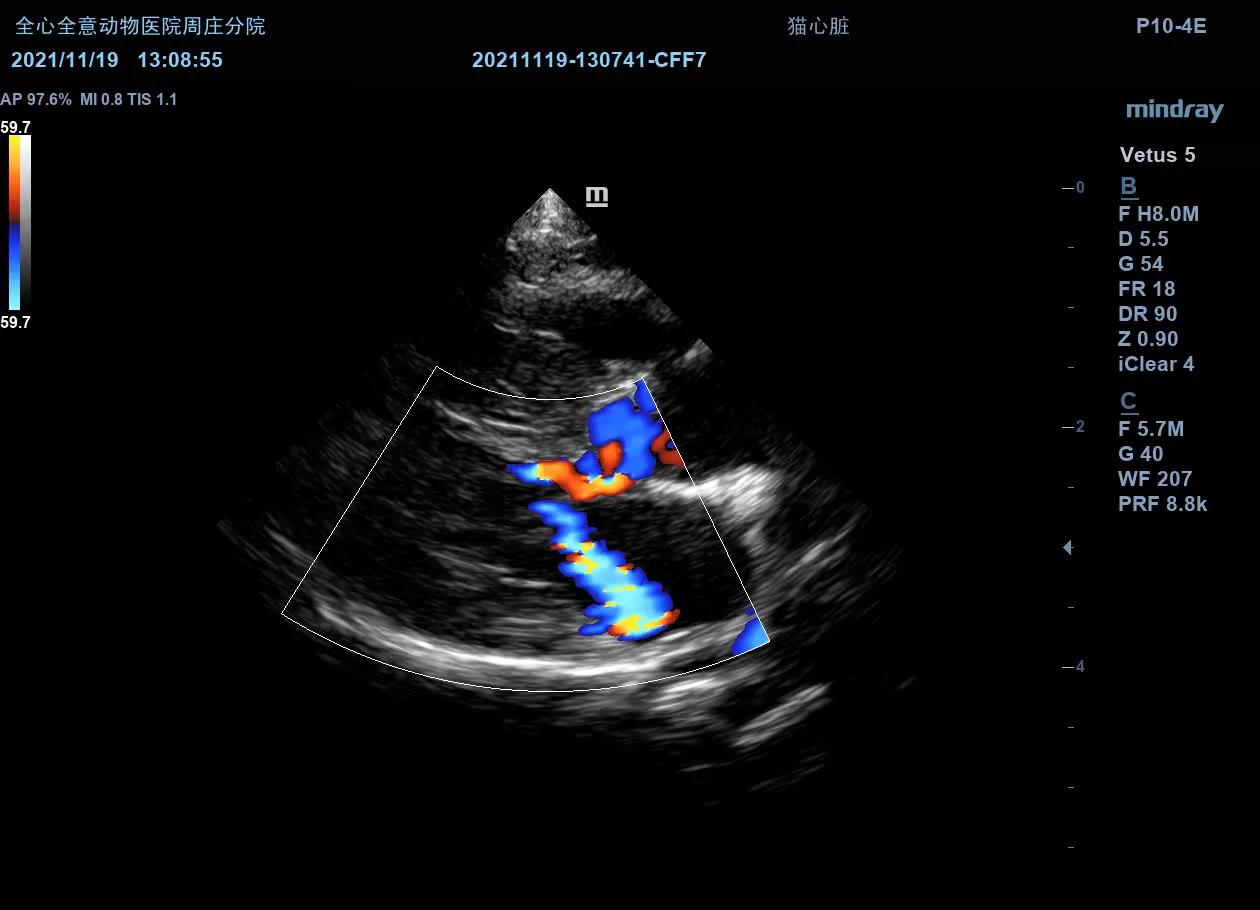

右侧左室流出道观:

左室不均匀性增厚,心尖最为明显。可见乳头肌增大异常,腱索连接异常,室间隔基部异常向左心室内增大,导致左室流出道前窄后宽。左心房主观增大。color模式下收缩期可见左室流出道以红色为主的花色血流信号,左房可见蓝色为主的花色血流信号。

左侧心尖四腔(color):

可见收缩期二间瓣反流信号。

MR Vmax:4.07m/s

左侧测量瓣膜口流速正常。